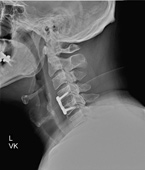

Before

After